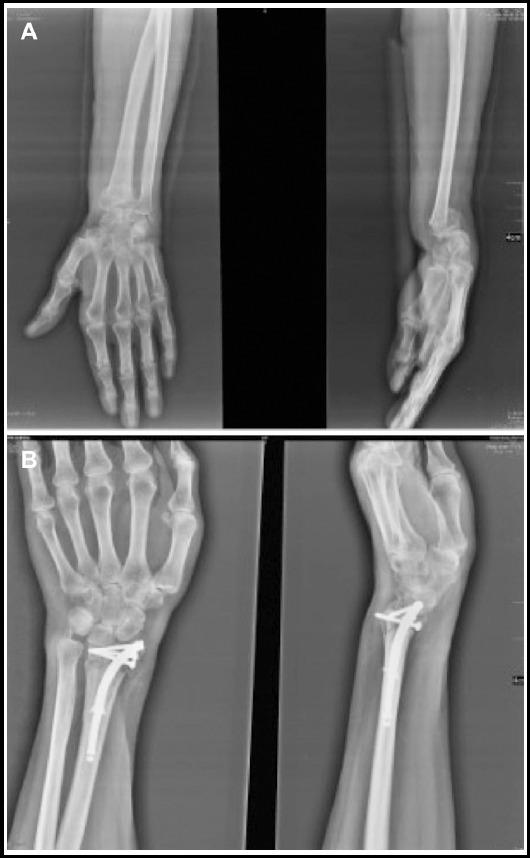

成人患者使用可扩张髓内钉系统固定不稳定桡骨远端骨折

Fixation of unstable distal radius fractures by using expandable Intramedullary nailing system in adult patients.

To present our experience on intramedullary nailing device Sonoma Wrx (Sonoma Orthopedic Products Inc., Santa Rosa, CA, USA) used for internal fixation of extra-articular or simple intra-articular distal radius fractures in adult population.

This study was conducted from February 2011 to October 2016. A total of 48 patients (mean age 47.3±5.6 years, 35.4% females) with distal radius fracture, who underwent intramedullary distal radius fixation by using Sonoma Wrx were included in this retrospective study. Clinical outcome measures (range of motion [ROM], visual analog scale [VAS]), functional outcomes (Disabilities of the Arm, Shoulder and Hand [DASH] score and Gartland-Werley score), radiographic scores (Stewart score) and parameters (radial inclination, volar tilt, radial height, radio-ulnar variance) and complications were evaluated.

The total surgery time was 24.3±2.3 minutes. Patients were followed up for 24.7±3.4 weeks. Complete fracture union was obtained at 5.5±0.9 weeks. The postoperative low VAS pain score (1.6±0.93) and high ROM values (76.7° for extension, 78.5° for supination, 80.1° for flexion, and 82.3° for pronation) indicated a very good clinical outcome. DASH score of 8.3±1.5 and Gartland-Werley score of 2.8±4.1 showed good functional outcome. The radiographic Stewart score was 1.0±1.2. Radial inclination, volar tilt, and radial height significantly increased (p<0.001), and radio-ulnar variance decreased (p=0.001) with surgery. No postoperative complication was recorded in 40 patients (83.3%).

Sonoma Wrx, which is an expansible intramedullary elastic locking distal radius nail, offers a good alternative technique for internal fixation of unstable distal radius fractures with the advantage of minimum soft-tissue dissection and related postoperative complications.